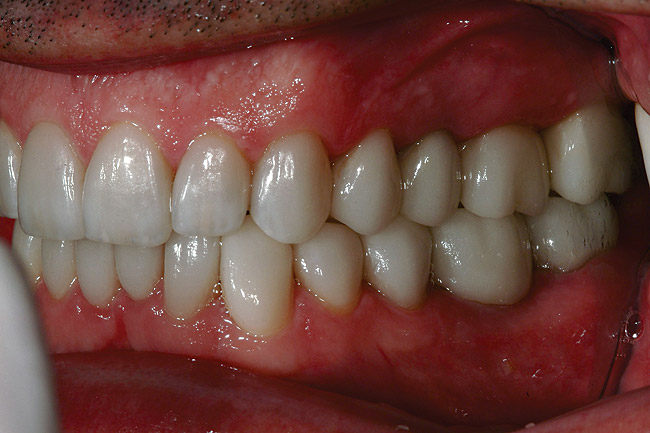

Figure 36   Retracted left postoperative view of the IPS e.max restorations.

Figure 36

Figure 38  Retracted right postoperative view of the IPS e.max restorations.

Figure 38